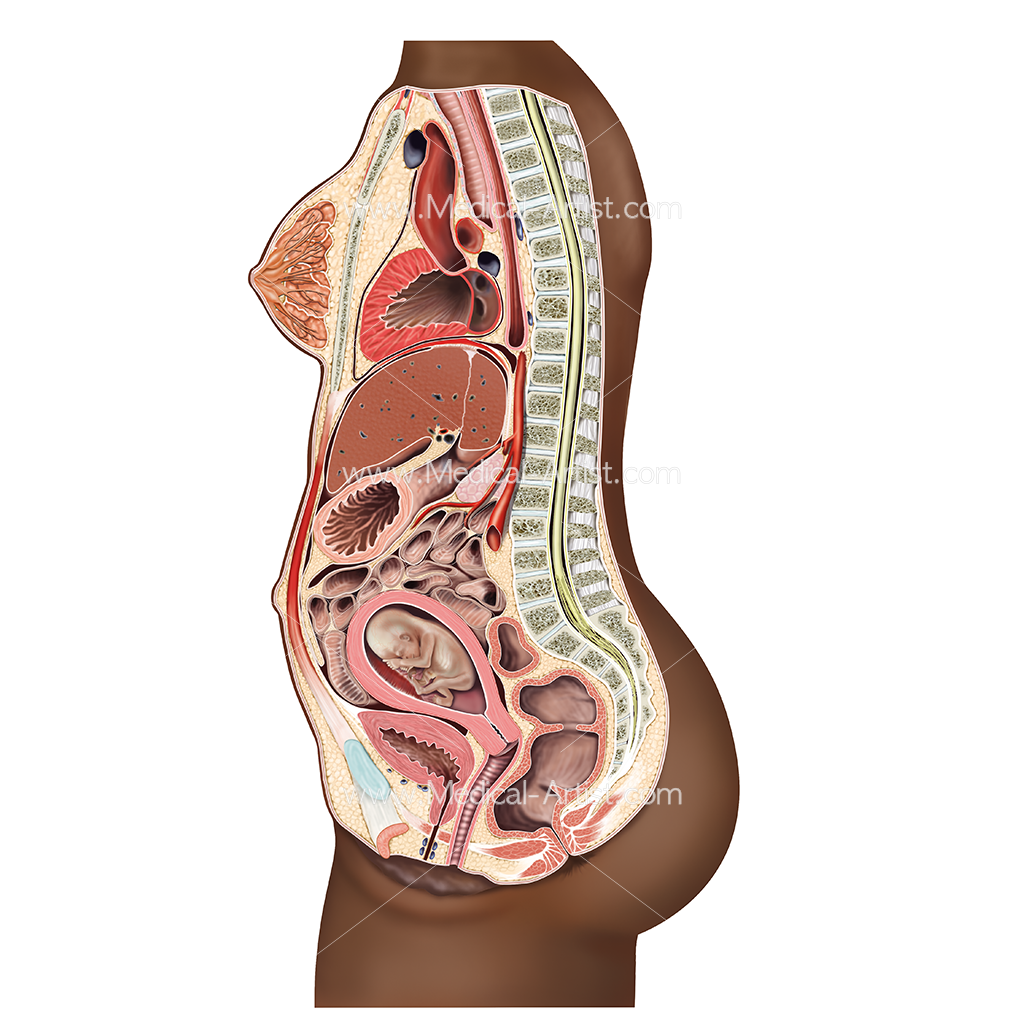

Физиология беременности: строение органов

Раздел: Моменты озарения